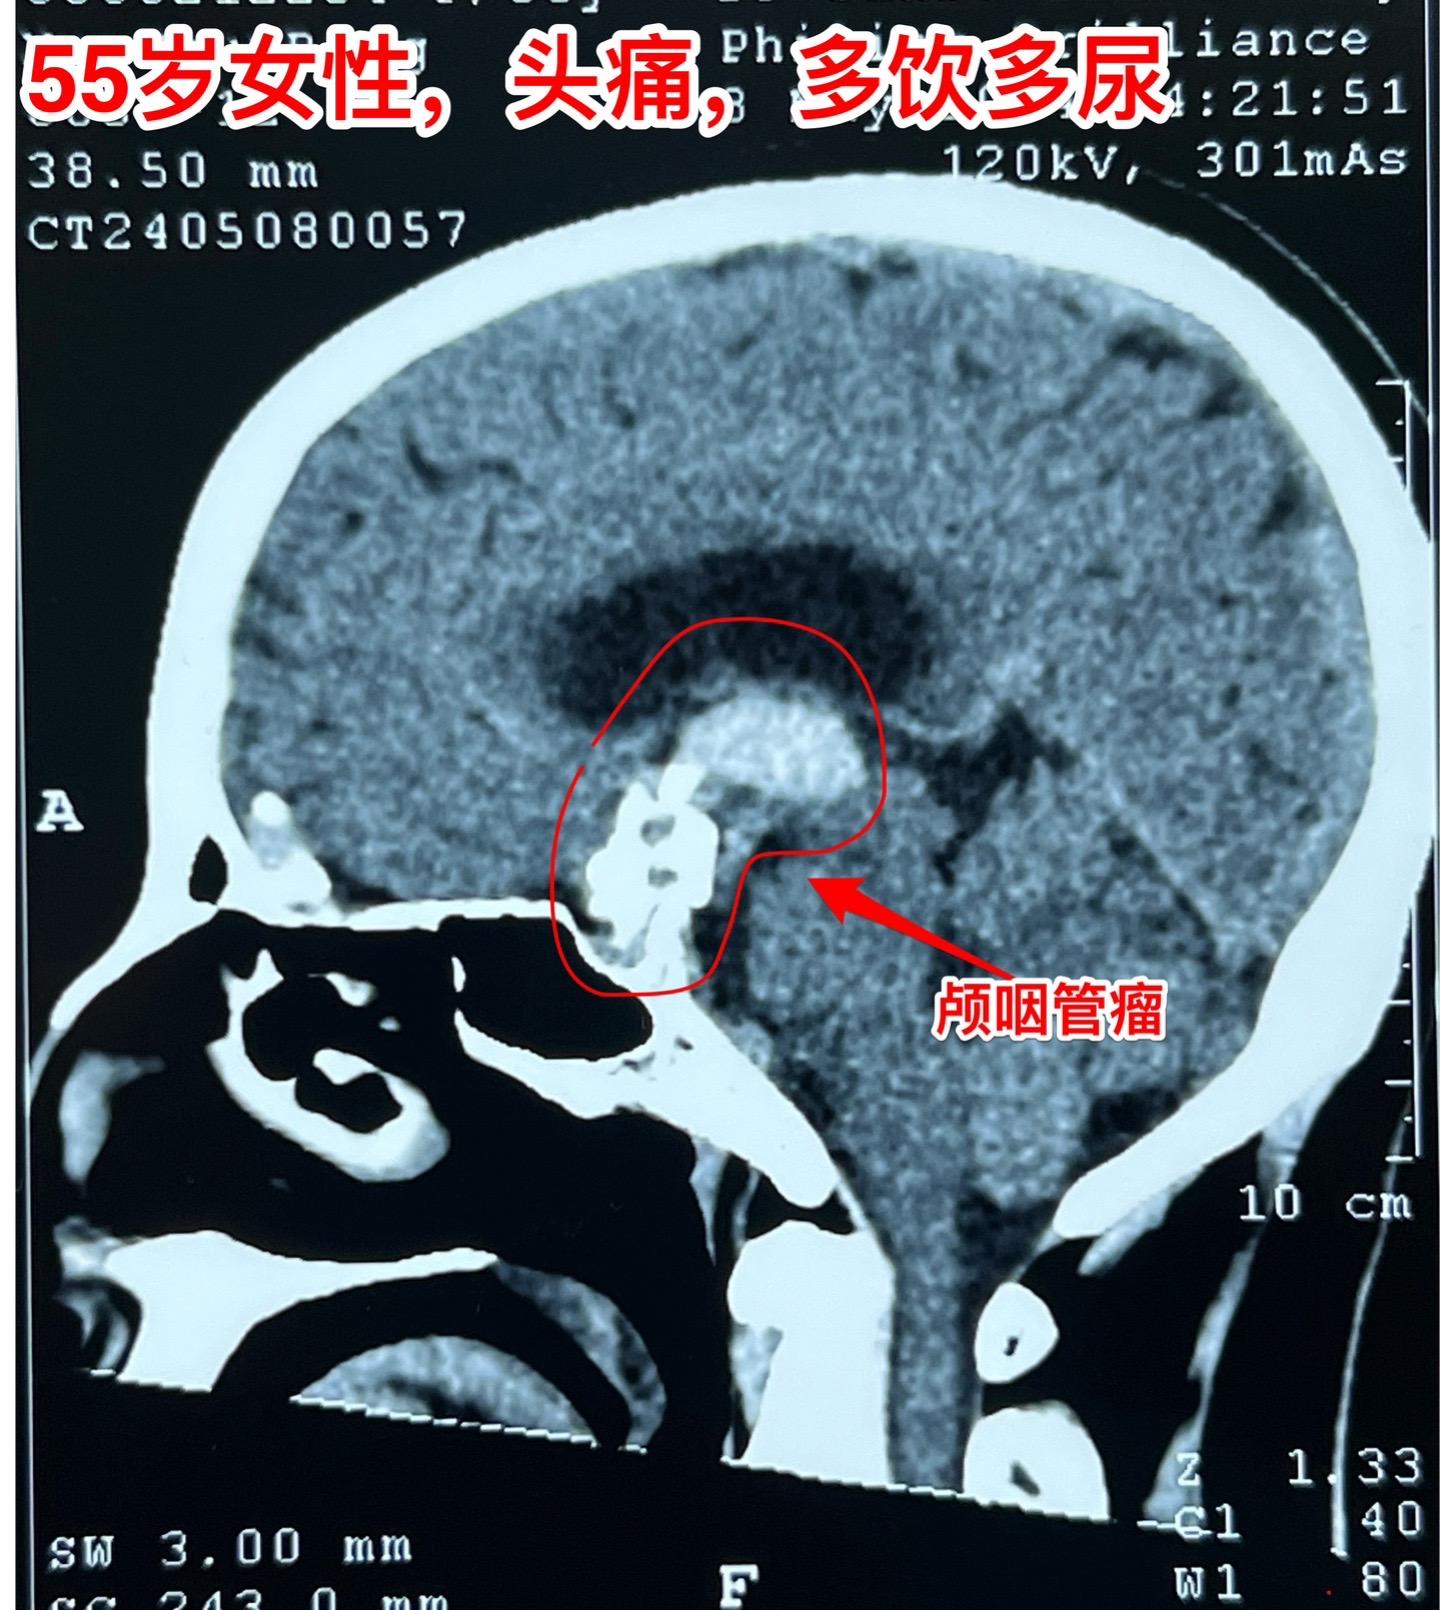

5月16日两个颅咽管瘤手术。五一假期后开展的手术都是颅咽管瘤切除手术。经常一天作两个颅咽管瘤手术!这样的劳动强度有点大! 5.16一天两个颅咽管瘤手术,肿瘤有相似的特征,两个都有大块的钙化斑;都是从垂体柄侵入垂体中;手术方式也相似-经额底纵裂入路。 手术后两个病人都顺利从ICU转移到普通病房。

5月16日两个颅咽管瘤手术。五一假期后开展的手术都是颅咽管瘤切除手术。经常一天作两个颅咽管瘤手术!这样的劳动强度有点大! 5.16一天两个颅咽管瘤手术,肿瘤有相似的特征,两个都有大块的钙化斑;都是从垂体柄侵入垂体中;手术方式也相似-经额底纵裂入路。 手术后两个病人都顺利从ICU转移到普通病房。颅咽管瘤